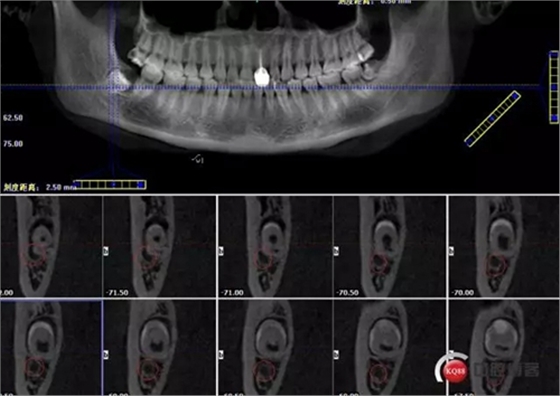

牙齒中1/3神經(jīng)管偏頰側(cè)